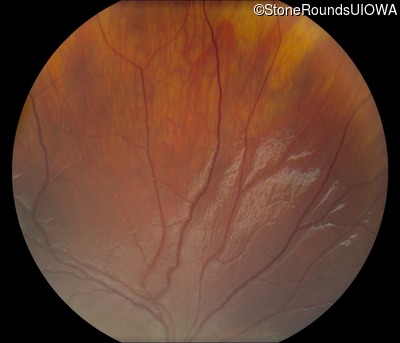

Visit at age: 11 years

Fundus Photography - Left - 20/50 -2

Exemplar